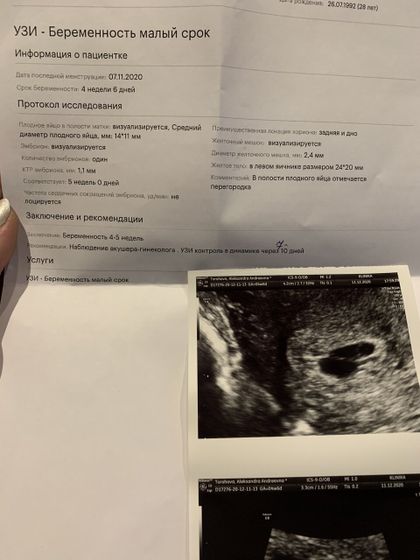

Смотрели меня сегодня на узи и сразу же сказала есть эмбриончик все хорошо! Скорее всего у меня была раняя овуляция!

И самое удивительное она сказала что мое плодное яйцо разделяется… но во втором мешочке пока нет эмбриончика… и она сказала через неделю придти и все будет понятно два или все таки один… и хгч она сказала достаточно большое было в день моих месячных (похожа на двойню) я прибываю в шоке… чувство радости сколько бы их там не было все мои будут, мои родные бусинки ♥️

Главное все в норме, маточная Беременность! Через неделю уже будет сердечко ?

Да, когда на второе узи поехала уже был один )) а вот почему думали что двое фото прикреплю

Нет ещё он только появился я так понимаю, сказали через неделю приехать уже сердце будет точно… и возможно уже второй эмбрион будет